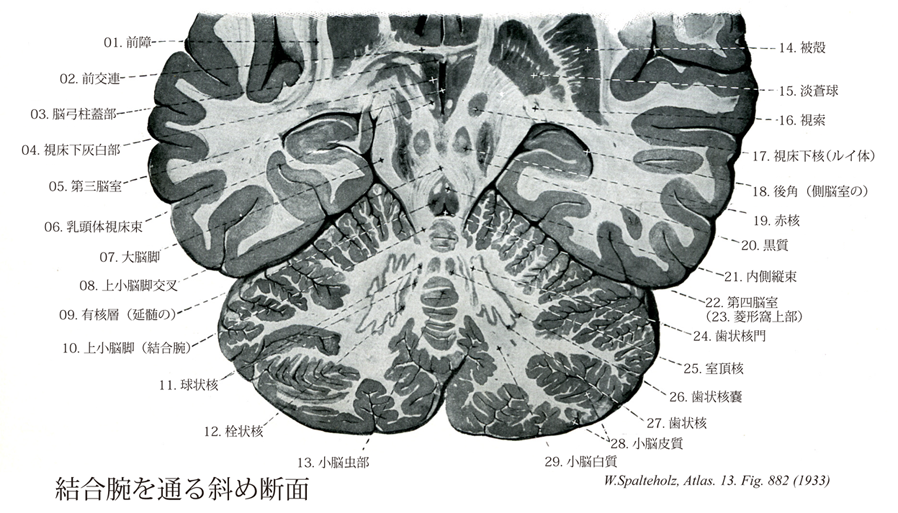

882

- 882_08Wernekink's decussation【Decussation of superior cerebellar peduncles上小脳脚交叉;結合腕交叉;小脳大脳脚交叉;大被蓋交叉 Decussatio pedunculorum cerebellarium superiorum; Decussatio crurum cerebellocerebralium】 Crossing of the peduncles below the inferior colliculus and ventral to the medial longitudinal fasciculus.

→(上小脳脚は小脳核から出て初めは表面を走るが、下丘の高さで奥に入り交叉して一部は対側の赤核に終わり、一部は視床に至る。この交叉を上小脳脚交叉という。)

- 882_10【Superior cerebellar peduncle (Brachium conjunctivum)上小脳脚;結合腕;小脳大脳脚 Pedunculus cerebellaris superior; Brachium conjunctivum; Crus cerebellocerebrale】

→(上小脳脚(結合腕Brachium conjunctivum)は主として小脳を出る線維からなる。その主体をなす線維は小脳視床路と小脳赤核路である。これらは主として歯状核から出て、腹内側方に進んで深部に入り、中脳下半で大部分交叉し、上小脳脚交叉(結合腕交叉)を作り、反対側の中脳被蓋を上行し、一部は赤核に終わるが(小脳赤核路)、一部はさらに視床の前外側腹側核に至る(小脳視床路)。なお上小脳脚の表面を前脊髄小脳路が逆行して小脳に入り、主としてその前葉に分布する。また鈎状束は室頂核から出て大部分交叉し、上小脳脚の背外側をへて鈎状に曲がり、下小脳脚内側部の上部に来て前庭神経各核にならびに橋、延髄の網様体内側部に分布する。)

- 882_11【Globose nucleus; Posterior interpositus nucleus球状核;後中位核 Nucleus interpositus posterior; Nucleus globosus】 Collection of cells lying medial to the dentate nucleus.

→(球状核は2~3個の円い細胞集団で、栓状核の内側、室頂核の外側に位置する。ここには大型および小型の多極細胞がある。下等哺乳動物では栓状核と球状核は連続しているように見え、これらを一括して中位核とよぶ。その組成細胞および線維連絡の違いにより、これはヒトの、①栓状核に相当する前中位核と、②球状核に相当する後中位核に区別される。)

- 882_24【Hilum of dentate nucleus歯状核門;歯状核口 Hilum nuclei dentati】 Opening of the dentate nucleus that gives exit to the majority of fibers forming the superior cerebellar peduncle.

→(小脳の歯状核門は小脳のフラスコ状歯状核門で、内方を向き、上小脳脚または結合腕をつくる線維群に出口を与えている。)

- 882_27【Dentate nucleus; Nucleus lateralis cerebelli歯状核;小脳外側核 Nucleus dentatus; Nucleus lateralis cerebelli】 Largest cerebellar nucleus. It resembles a folded pouch and is situated in the white substance of cerebellum.

→(歯状核は小脳核の中で最も外側にある最も大きい核。小脳半球の白質中に位置する。この核は横断切片では渦巻形の灰白質が袋状に並び、袋の口(歯状核門)が内側方に向かい、下オリーブ複合核によく似ている。核は主に大型で多くの分枝した樹状突起をもつ多極細胞よりなる。より内側に位置している球状核や栓状核とともに、上小脳脚または結合腕を形成する線維の主な起始をなす。)